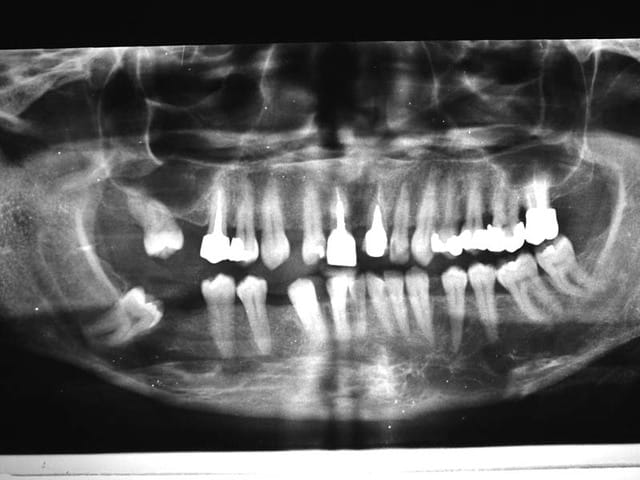

je viens de recevoir les Rx.

Dscf0773 s5e52w - Eugenol

Dscf0774 n8peyh - Eugenol

Image odged8 - Eugenol

Patient brachy, tendance Cl. III.

Pas de Pb. Paro

Pas de déviation du chemin d’ouverture

Ce n’est pas une occlusion que je construirais, aussi je ne vais pas la détruire pour le faire rentrer dans des normes qu’il supportera peut être moins bien

Donc

Refermer l’espace 42/43

Remettre 43 en Cl. I. regler 43/13, là je peux peut etre utiliser les filtres (si le secret défense est levé)

Réaligner les Inc. Inf.

Et mon confrere pourra refaire les dents

@+ Bjc.